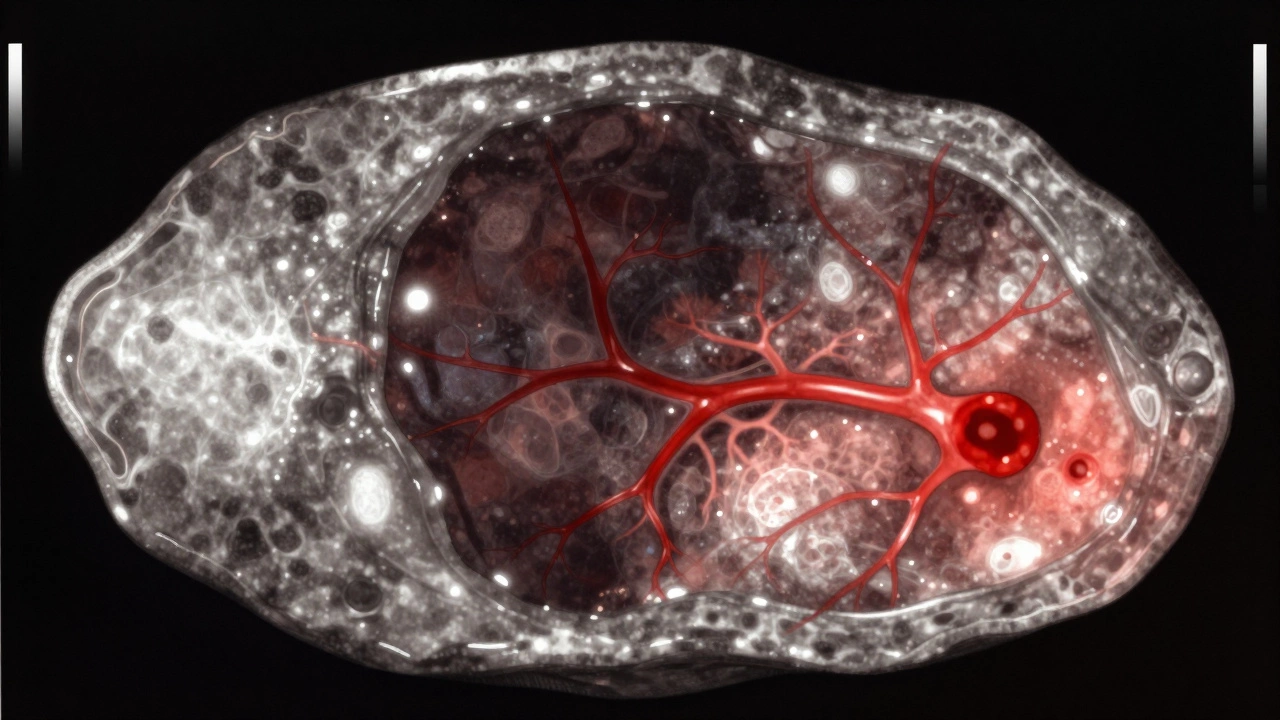

Опухоль - это плотная ткань, которая растёт изнутри органа. На УЗИ она не чёрная. Она светлее, сероватая или беловатая, с неровными, нечёткими границами. Внутри может быть неоднородная структура: одни участки плотнее, другие - мягче. Часто в опухоли видны кровеносные сосуды - врач включает режим допплерографии и видит, как кровь течёт внутри образования. Это важный признак. Киста не должна иметь кровотока. Если кровоток есть - это сигнал, что ткань активно растёт, и это может быть опухоль.

4. Кровоток - если в образовании есть сосуды (видно на допплере), это почти всегда опухоль. Киста не имеет кровеносных сосудов внутри.

УЗИ опухоли: неровные границы, включения и кровоток внутри образования.